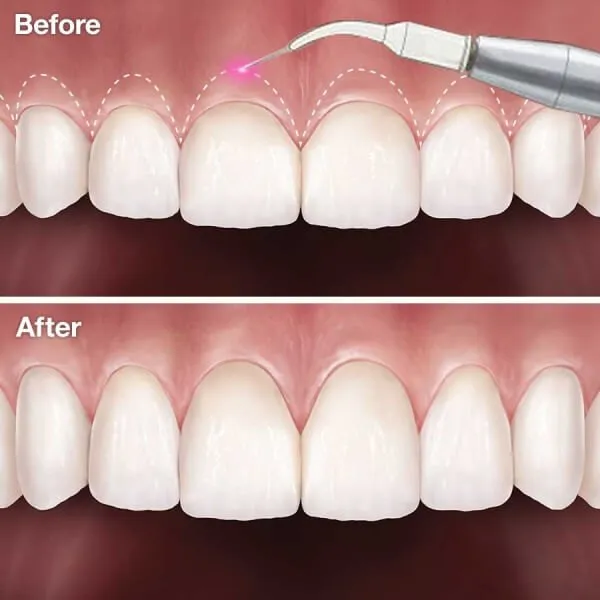

Cắt lợi là một kỹ thuật nha khoa được thực hiện để hạn chế các bệnh liên quan đến lợi. Những trường hợp như hở lợi, viêm